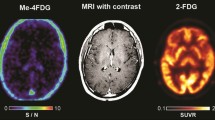

We have conducted Me4FDG PET scans on human subjects, including eight glioblastoma patients, three pancreatic cancer patients, and several prostate cancer patients. In healthy people, Me4FDG did not enter the brain as expected because of the absence of SGLTs in the normal blood-brain barrier and the fact that Me4FDG is not a substrate for GLUT1 in the blood barrier (Fig. 4) [24]. While Me4FDG does not enter the brain across the blood-brain barrier, it should be noted that at least in rodents, functional SGLTs are expressed throughout the brain, including the cortex, cerebellum, and hippocampus [26, 27]. Another major difference between Me4FDG and 2FDG PET is that the Me4FDG is not excreted in the urine (see [24]). There was minor Me4FDG accumulation in the skeletal muscle, kidney cortex, and liver, but, at least in mice, this was not due to SGLT1 or SGLT2 activity [18, 19].

Me-4FDG and MRI scans on a control subject. Scans were conducted on a 24-year-old male patient with a history of epilepsy. The MRI (T1-weighted MP-RAGE with and without gadolinium contrast) was carried out as part of his clinical care. The brain Me4FDG PET scan 30 min after intravenous injection of 370 MBq Me4DG was conducted on a Siemens Biograph PET/CT scanner. The SUVR/BG scale, 0–10, is shown for the NIH color scale. Revised from Kepe et al. [10]

In patients with WHO stage III and IV glioblastomas, Me4FDG does enter the brain across the blood-tumor barrier and accumulates in active tumor (Fig. 5). For comparison, the figure also shows the MRI and 2FDG PET images for this patient. The MRI images indicate that the blood-tumor barrier is disrupted for gadolinium, as is likely for Me4FDG. In dynamic PET scans, there was no evidence for Me4FDG washout from the tumor, indicating that indeed the tracer was accumulated in active tumor and not simply by passive entry into the tumor through the blood-tumor barrier. Me4FDG was restricted to the tumor, but 2FDG uptake was seen in the tumor and throughout the brain, especially in regions of high metabolic activity such as the cerebral cortex. Similar results were obtained on eight other patients with WHO stage III or IV glioblastomas. In general, the level of Me4FDG in tumors was 14 times higher than the background level in the brain parenchyma and 2 times higher than in blood. In terms of the resolution, tumors as low as 6 mm in diameters have been detected [10]. In the three patients with pancreatic adenocarcinomas studied so far, we were unable to detect any Me4FDG tumor accumulation.

Me4FDG PET, MRI, and 2FDG PET scans on a WHO grade IV astrocytoma patient. The 57-year-old male patient has a 46-mm posterior corpus callosum astrocytoma. The Me-4FDG scan was conducted as for that on the control subject (Fig. 4) and shown as the S/N (SUVR/BG) ratio relative to the torcula on the NIH color scale. The standard clinical 2FDG PET brain scan is s for the “hot iron” on the SUVR based on a reference region of the brain. Taken from Kepe et al. [10]

SGLT2 Na+/glucose cotransporters are expressed in human pancreatic and prostate adenocarcinomas as judged by in vitro Me4FDG uptake assays and immunocytochemistry and by mouse in vivo models as shown by Me4FDG micro-PET, ex-vivo autoradiography, and immunocytochemistry. In patients, Me4FDG uptake into high-grade glioblastomas was also observed in PET studies, and this was correlated with positive SGLT2 immunocytochemistry on malignant cells and tumor vasculature. At this time, the significance of SGLT2 expression in tumors is not known, but at a minimum, Me4FDG PET offers significant advantages over conventional 2FDG PET in imaging advanced glioblastomas (see Fig. 5). Studies are underway to test the effect of SGLT2 drugs on glucose uptake into tumors in patients, and this may lead to clinical trials to test SGLT2 drug therapy for tumors.